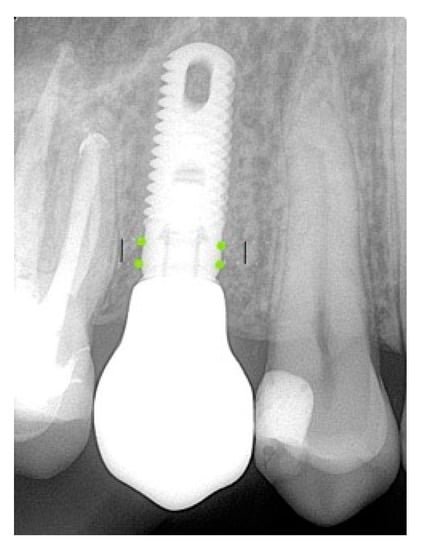

Using the parallel technique (Updegrave 1951), segmental radiography was performed by an experienced X-ray technician for each patient. Digital measurements of the bone loss level were performed in the event of definitive prosthetics and at 1 year. The platform of the implant was taken as a reference point. Two lines parallel to the implant descended medially and distally to the level of the first thread, which was in contact with the bone (Figure 4).

Figure 4. Measurement of the bone loss level.